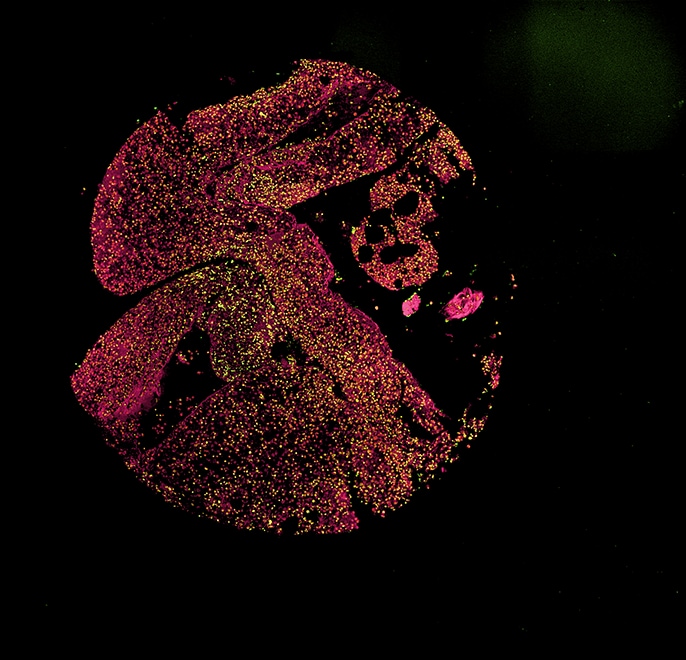

Eine Besonderheit der Arbeitsgruppe sind die eigens entwickelten Tissue Microarrays (TMAs) von MDS-Knochenmark-Stanzbiopsien, auf denen zum direkten Vergleich auch Biopsien von Patienten mit AML (akute myeloische Leukämie) sowie normale Kontrollen enthalten sind. Für die Auswertung von immunhistochemischen Untersuchungen an den TMAs ist ein großer Vorteil des Fluoreszenzmikroskops BZ, dass eine – oder sogar mehrere – Proben auf dem TMA zusammenhängend in einem Bild erfasst werden können.

„Die Stitching-Funktion ist dabei für uns besonders wichtig, um den 2 mm großen Core in einem Bild darstellen zu können“, erklärt Norbert Gattermann.

Norbert Gattermann und seine wissenschaftlichen Mitarbeiter*innen forschen zu Protein-Interaktionen an der inneren Mitochondrien-Membran und in der Matrix, um herauszufinden, warum das Eisen und das Porphyrin nicht richtig zusammenkommen. Mit dem Fluoreszenzmikroskop BZ werden Membrankomplexe auf strukturelle Anomalien untersucht, indem Protein-Protein-Interaktionen mit dem Proximity Ligation Assay (PLA) als Fluoreszenzsignale sichtbar gemacht werden. Die Sectioning-Funktion ermöglicht klare Aufnahmen ohne Fluoreszenzunschärfe. Es werden nur die Signale aus den fokussierten Ebenen extrahiert und daraus eine tiefenscharfe Aufnahme erzeugt. Die untersuchten Protein-Interaktionen betreffen die Ferrochelatase und ihre, zum Teil nur temporären, Interaktionspartner im „mitochondrial heme metabolism complex“.